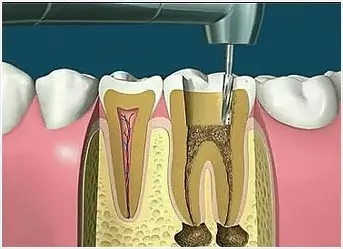

4、根管預(yù)備

根管清理成形的目的是去凈根管壁上的感染物,通過根管器械的切削作用去除感染的牙本質(zhì)并清理根管壁細菌以利于根管充填。